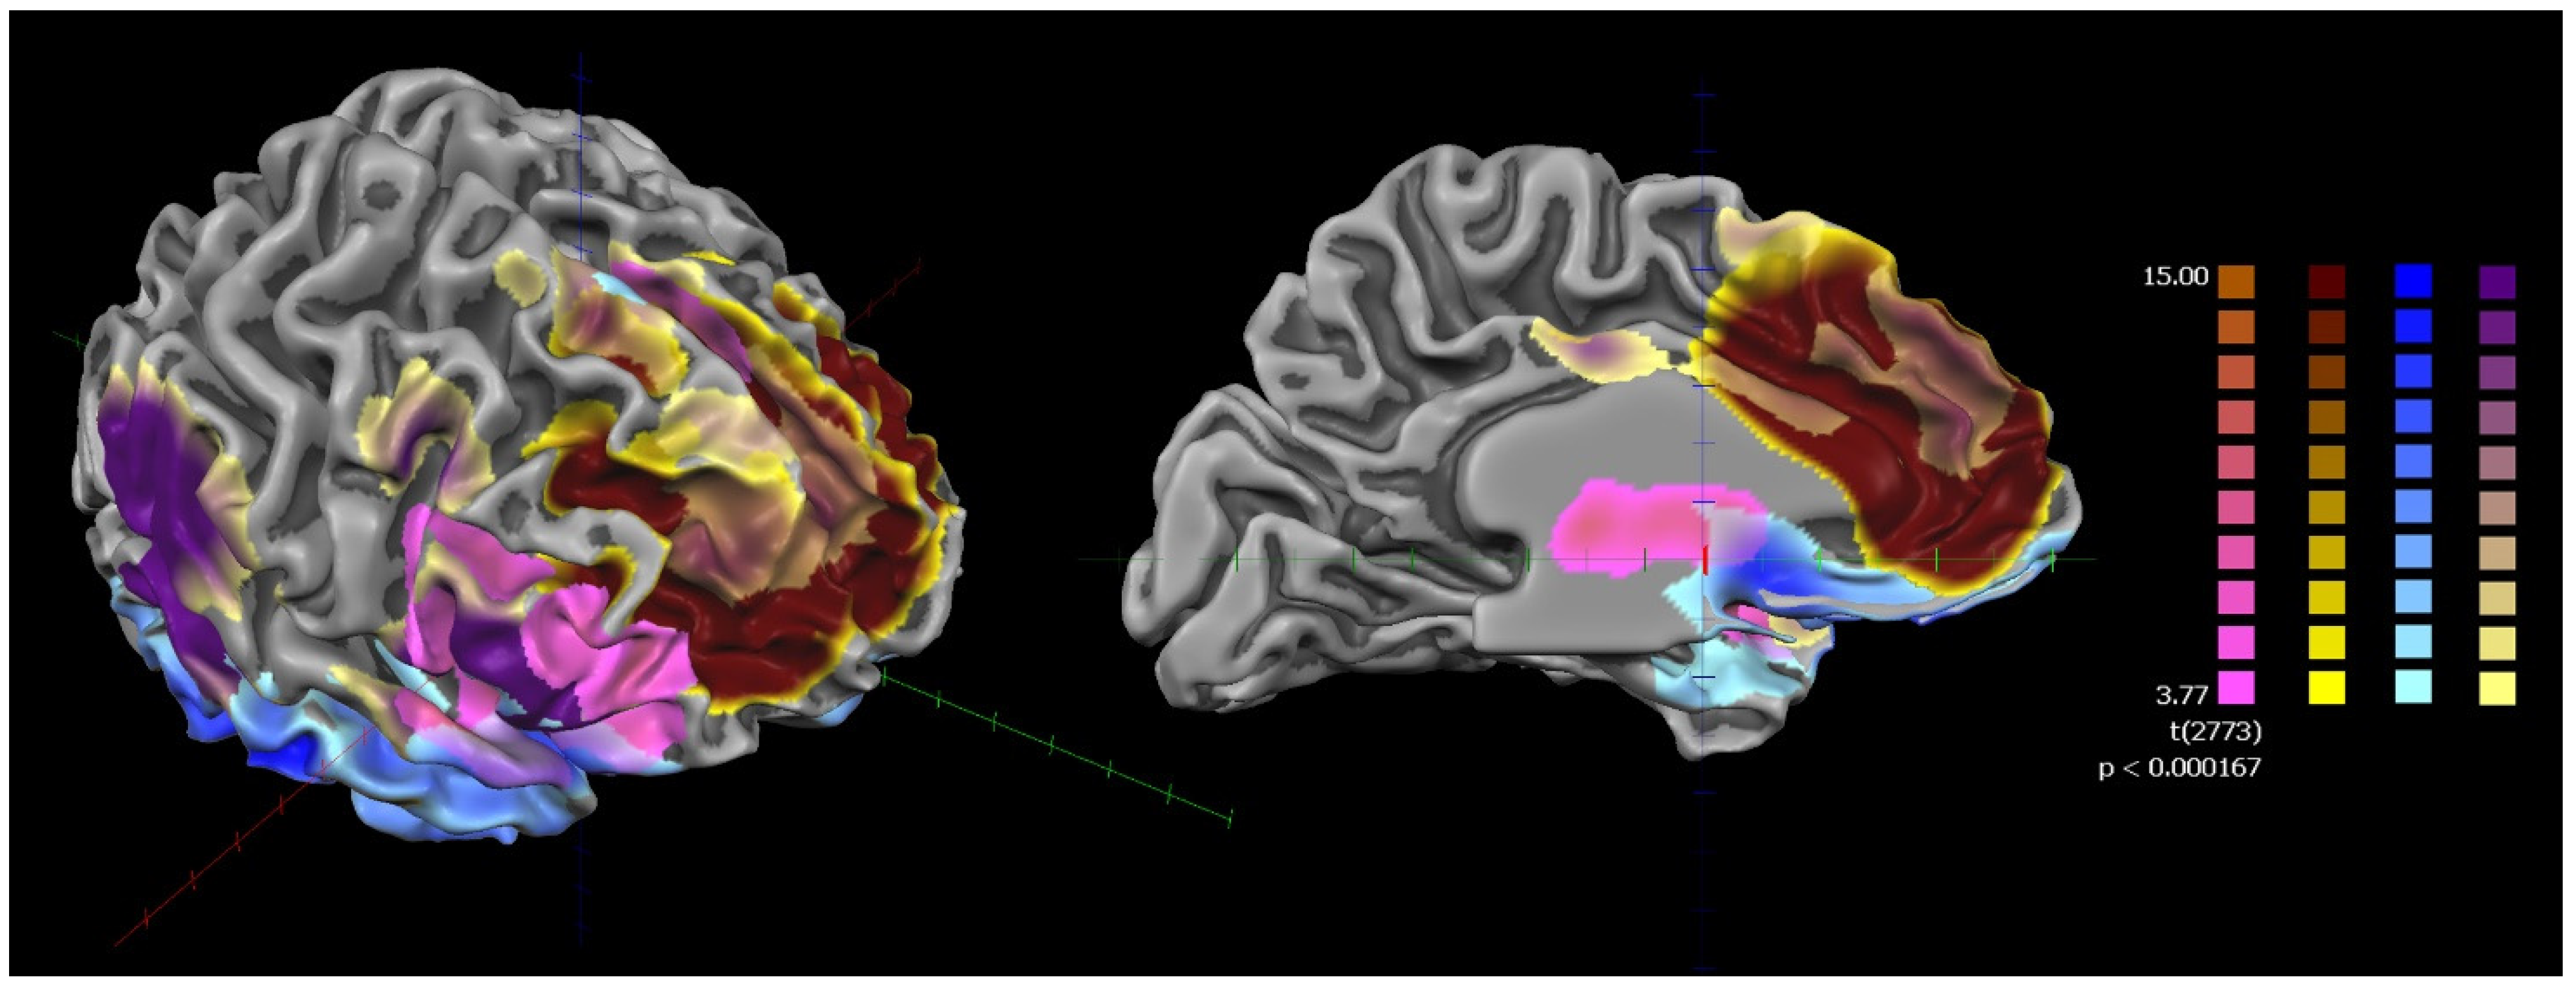

None of the subjects were excluded from falling asleep during the scan. The results of the rsFC of the bilateral FIC and bilateral l-ACC in the whole sample (HCs and SZ) showed that they were part of a frontotemporal network mainly involving the bilateral ACC, insulae, and prefrontal and supplementary motor cortices (Figure 2).

Figure 2.

ROI-based rsFC of cortical areas with the highest densities of VENs used as the seed (whole sample: HCs + patients with SZ). HCs: healthy controls; SZ: patients with schizophrenia; ROI-based rsFC of cortical areas with the highest densities of VENs used as the seed. Random-effects whole-sample map resulting from analysis of covariance (ANCOVA), controlling for age, gender, duration of illness, and chlorpromazine equivalents. Corrections for multiple comparisons performed at the cluster level using 1.000 Monte Carlo simulations (p < 0.05), leading to a cluster threshold of K > 22 voxels in the native resolution. The different colors represent the subclusters derived from the voxel-wise parceling of the ROI-generated functional network (fuzzy clustering).

Voxel-wise parceling (fuzzy clustering) decomposed the functional network into four clusters. These clusters were associated with four well-known functional networks, namely the salience network (ACC and insula), the superior frontal network (dorsomedial frontal cortex), the orbitofrontal network (ventromedial prefrontal cortex), and the central executive network (ACC, insula, dorsolateral prefrontal cortex, and supplementary motor area) (Figure 2 and Figure 3) [56].

Figure 3.

Two-dimensional maps of the subnetworks resulting from the voxel-wise parceling of the ROI-generated functional network (fuzzy clustering) of the whole sample (HCs + SZ). HCs: healthy controls; SZ: patients with schizophrenia. Connectivity-based parceling of the VEN-derived functional network. Each panel represents a probabilistic map of one of the four functional connectivity-defined subclusters. These subclusters were associated with four well-known functional networks: the salience network (A), the superior frontal network (B), the orbitofrontal network (C), and the central executive network (D). L = left; R = right; A = anterior; P = posterior.